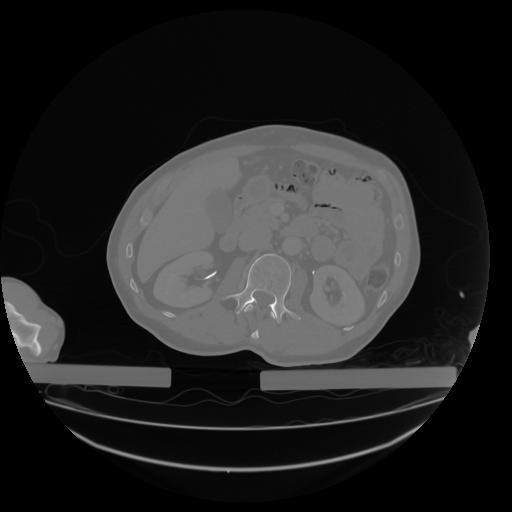

27 CUERPO,CE,Axial,3.0,CUERPO,,